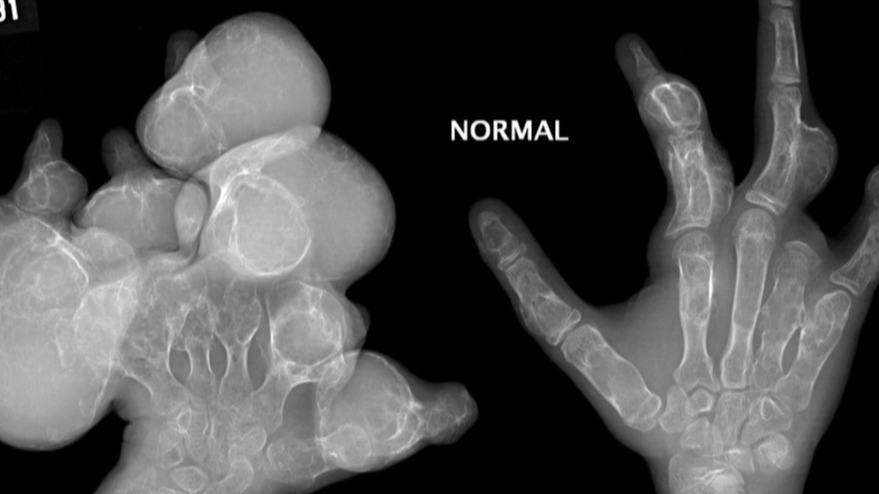

There are multiple lucent lesions, some with the classic rings and arcs calcification suggestive of chondroid lesions. There are areas of cortical destruction suggestive of extra-osseous extension of the lesions, which can be seen in the setting of malignant degeneration into chondrosarcoma.

This is a patient who was born in Scotland without significant family medical history. Early in childhood, he noticed small bony bumps over his right wrist. Upon medical consultation, wrist radiographs were performed and were diagnostic of enchondroma.

Over time, he developed other bony deformities of his extremities, ribs, and maxillary sinuses. These lesions were monitored via radiography and some required reconstructive surgery to help with functional outcome.